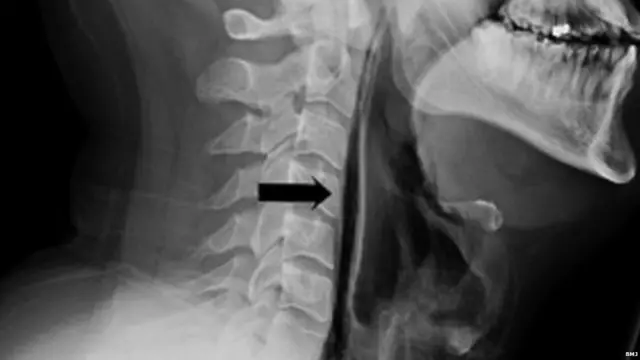

एक्स-रे में पता चला कि छींक रोकने की कोशिश के चक्कर में दबाव से श्वासनली की कोशिकाएं फट गई हैं.

इसके तुरंत बाद उनके गर्दन में तेज दर्द महसूस हुआ, कुछ निगलने में परेशानी आने लगी और यहां तक बोलना में भी मुश्किल हो रही थी. जब डॉक्टरों ने उन्हें चेक किया तो पता चला कि गले के आसपास गर्दन पर सूजन थी.